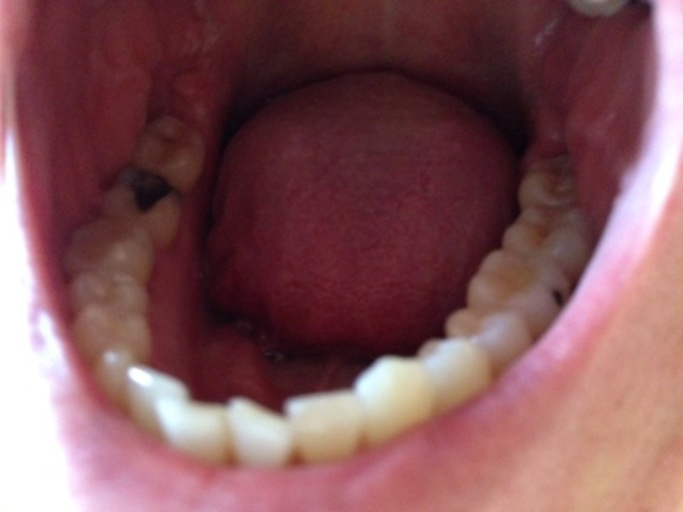

I'm having teeth troubles.

Hello my name is Abigail and I have been having a toothache on the right side of my mouth on my molars and it want go away and some spots on my gums are red . So what should I do. By the way I am 11 years old

Since you mentioned you are 11 years old, you may be experiencing the eruption of your second or 12 year molars.  This would explain the red spots on your gums as well if the tooth is breaking through the tissue.  It is important to let your parents know what you are experiencing and if the symptoms/pain is getting worse.  This will allow them to schedule a dental visit for you if necessary.